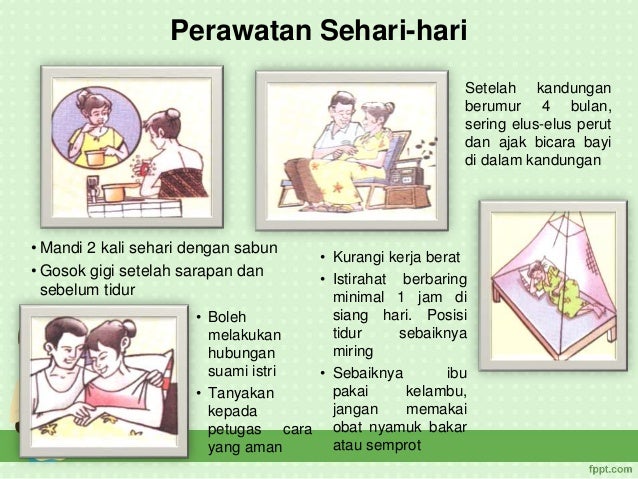

Ibu Hamil Dan Bayi Resti source: www.slideshare.net

Ibu Hamil Dan Bayi Resti source: www.slideshare.net